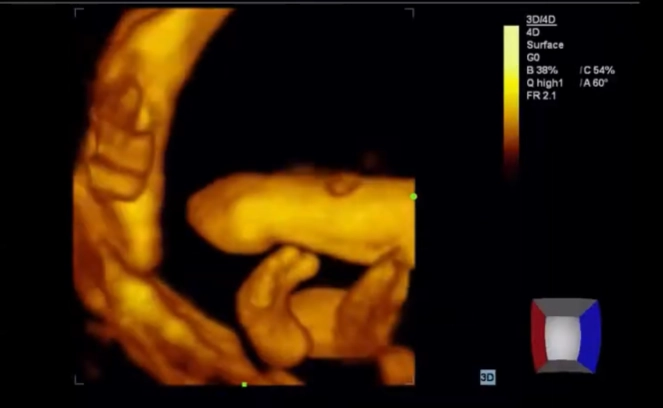

Cứng đa khớp bẩm sinh (Arthrogryposis Multiplex Congenita - AMC)/Chuỗi biến dạng do thai nhi bất động/giảm động (Fetal Akinesia/Hypokinesia Deformation Sequence - FA(H)DS)